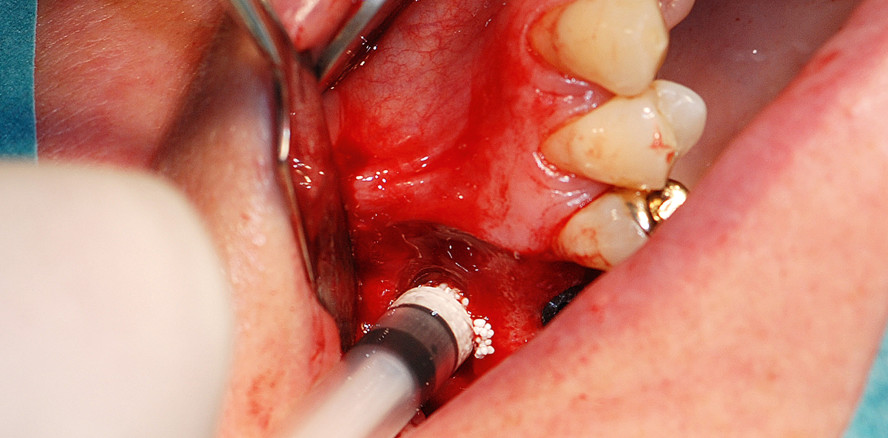

Der Eingriff erfolgte in Lokalanästhesie. Zunächst bildeten wir mittels eines nach palatinal verlagerten Krestalschnittes mit vertikalen Entlastungsinzisionen einen Mukoperiostlappen. Die Fenestrierung durch die vestibuläre Knochenwand des Sinus maxillaris, kranial der Regio 16 erfolgte mit dem SL1-Aufsatz für das Piezotome® (Acteon Satelec®) (Abb. 3), wir legten die Schnittführung dabei in einer nach kaudal abgeflachten Ellipse.

Mit dem SL3-Aufsatz (Elefantenfuß) lösten wir die Schneider’sche Membran vorsichtig zirkulär von den Schnittkanten (Abb. 4) und den frei­präparierten Knochendeckel von der Schleimhaut ab. Die Schleimhautdeckel wurden von Weichgeweberesten befreit und in Kochsalzlösung gelagert. Die Elevation der Membran erfolgte mit piezoelektrischen Aufsätzen und Hand­instrumenten (Abb. 5). Obwohl durch die oszillierende Schwingung der Aufsätze, welche sowohl die Membran bewegen kann als auch den Kavitationseffekt durch Vernebeln der eingesetzten Kühlflüssigkeit auslöst, ein sanftes Ausstreichen genügt, um die Membran sehr leicht bewegen und einen Hohlraum schaffen zu können, kam es zu einer Ruptur der Schleimhaut. Diese ist wahrscheinlich auf eine Vorschädigung der respiratorischen Membran durch frühere Entzündungen und die folgende Bildung von Narbengewebe zurückzuführen.